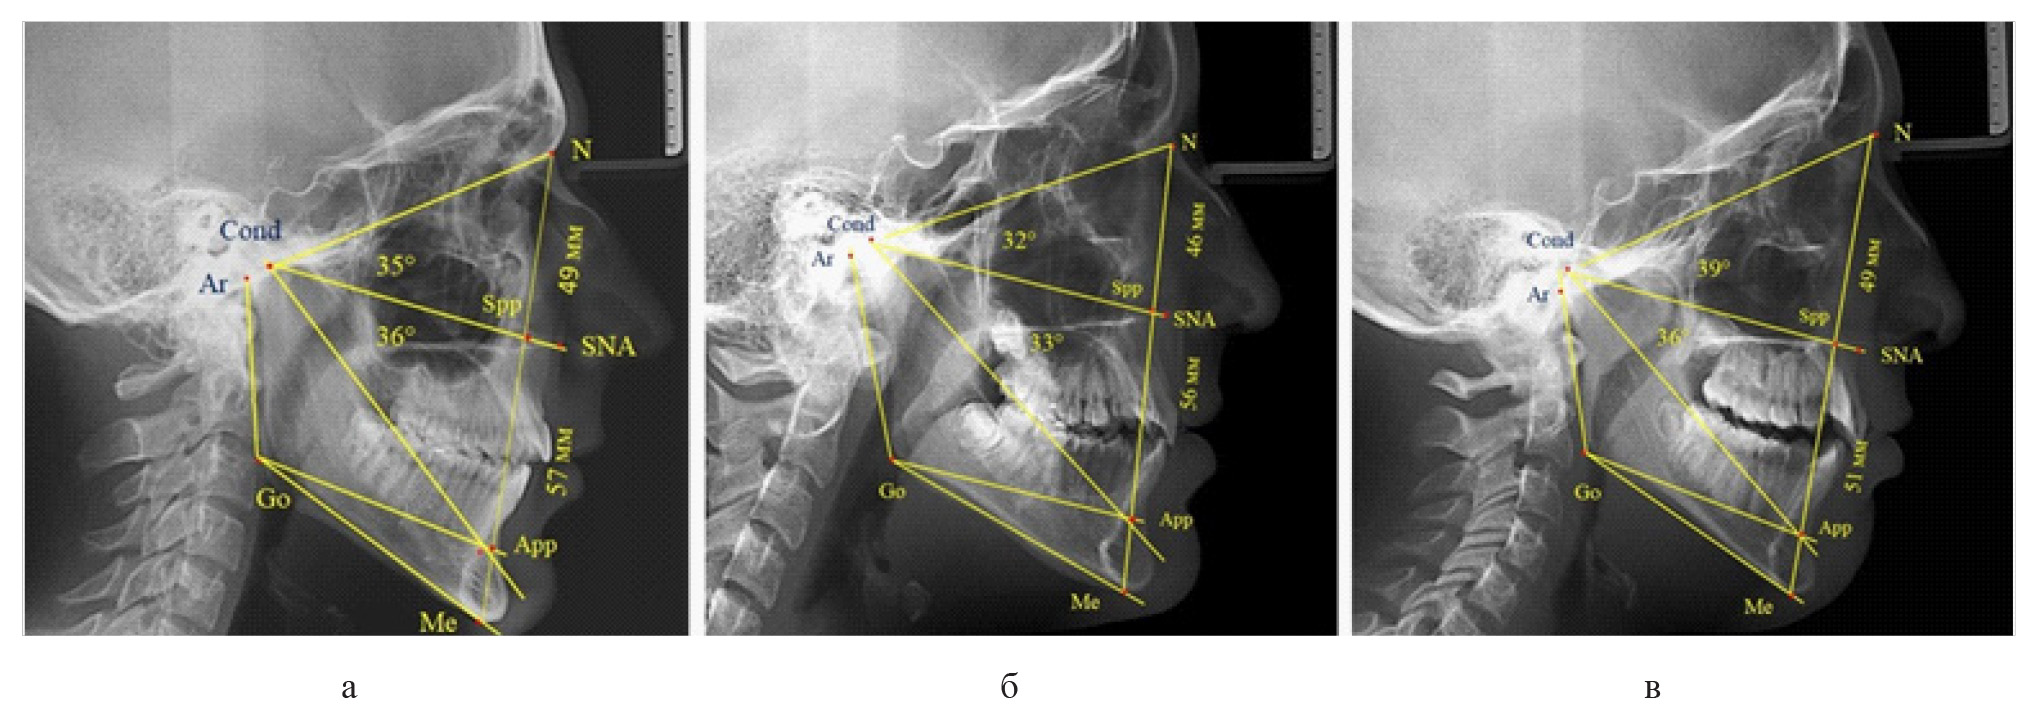

У 6 человек [(10,71 ± 4,13) %], отмечалось увеличение параметров гнатической части до уровня физиологического вертикального показателя, а у 2 человек [(3,57 ± 2,48) %], незначительное снижение гнатической части (рис. 3).

Рис. 3. Сравнительный анализ ТРГ с оптимальными размерами носового отдела и оптимальными (а), укороченными физиологическими (б) и увеличенными физиологическими (в) размерами гнатической части лица

Признаки снижения высоты назального отдела вплоть до уровня горизонтального патологического типа при физиологической окклюзии были определены у 10 человек [(17,86 ± 5,11) %]. При этом параметры гнатического отдела соответствовали физиологической норме либо физиологическому горизонтальному типу (рис. 4).

Рис. 4. Варианты ТРГ с укороченными размерами носового отдела и оптимальными (а) и укороченными (б) размерами гнатической части